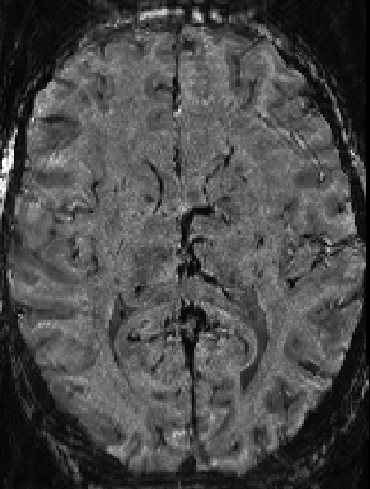

For partial Fourier imaging of 5/8 and 5/8, the effective resolution in the diagonal direction would be reduced to 28%. This means that a nominal resolution of 0.7 mm would in fact be 2.5 mm, instead! Through k-space zero-filling, this resolution would just be resampled (interpolated) to a 0.7 mm voxel grid.

For partial Fourier imaging of 6/8 and 6/8, the effective resolution in the diagonal direction would be reduced to 35%. This means that a nominal resolution of 0.7 mm would in fact be 2.0 mm, instead! Through k-space zero-filling, this resolution is just resampled (interpolated) to a 0.7 mm voxel grid.

For the use of layer-fMRI, it can be very valuable to obtain high resolution reference data, where the effective resolution is the same across all directions. Thus, I would highly recommend not to to use PF imaging in two directions at the same time. If you don’t have the time to do acquire the entire k-space in at least one phase encoding direction, I would suggest that it makes more sense to lower the matrix size and reduce the nominal resolution in the first place. In this way, the resolution reduction will as least be the same in all directions.